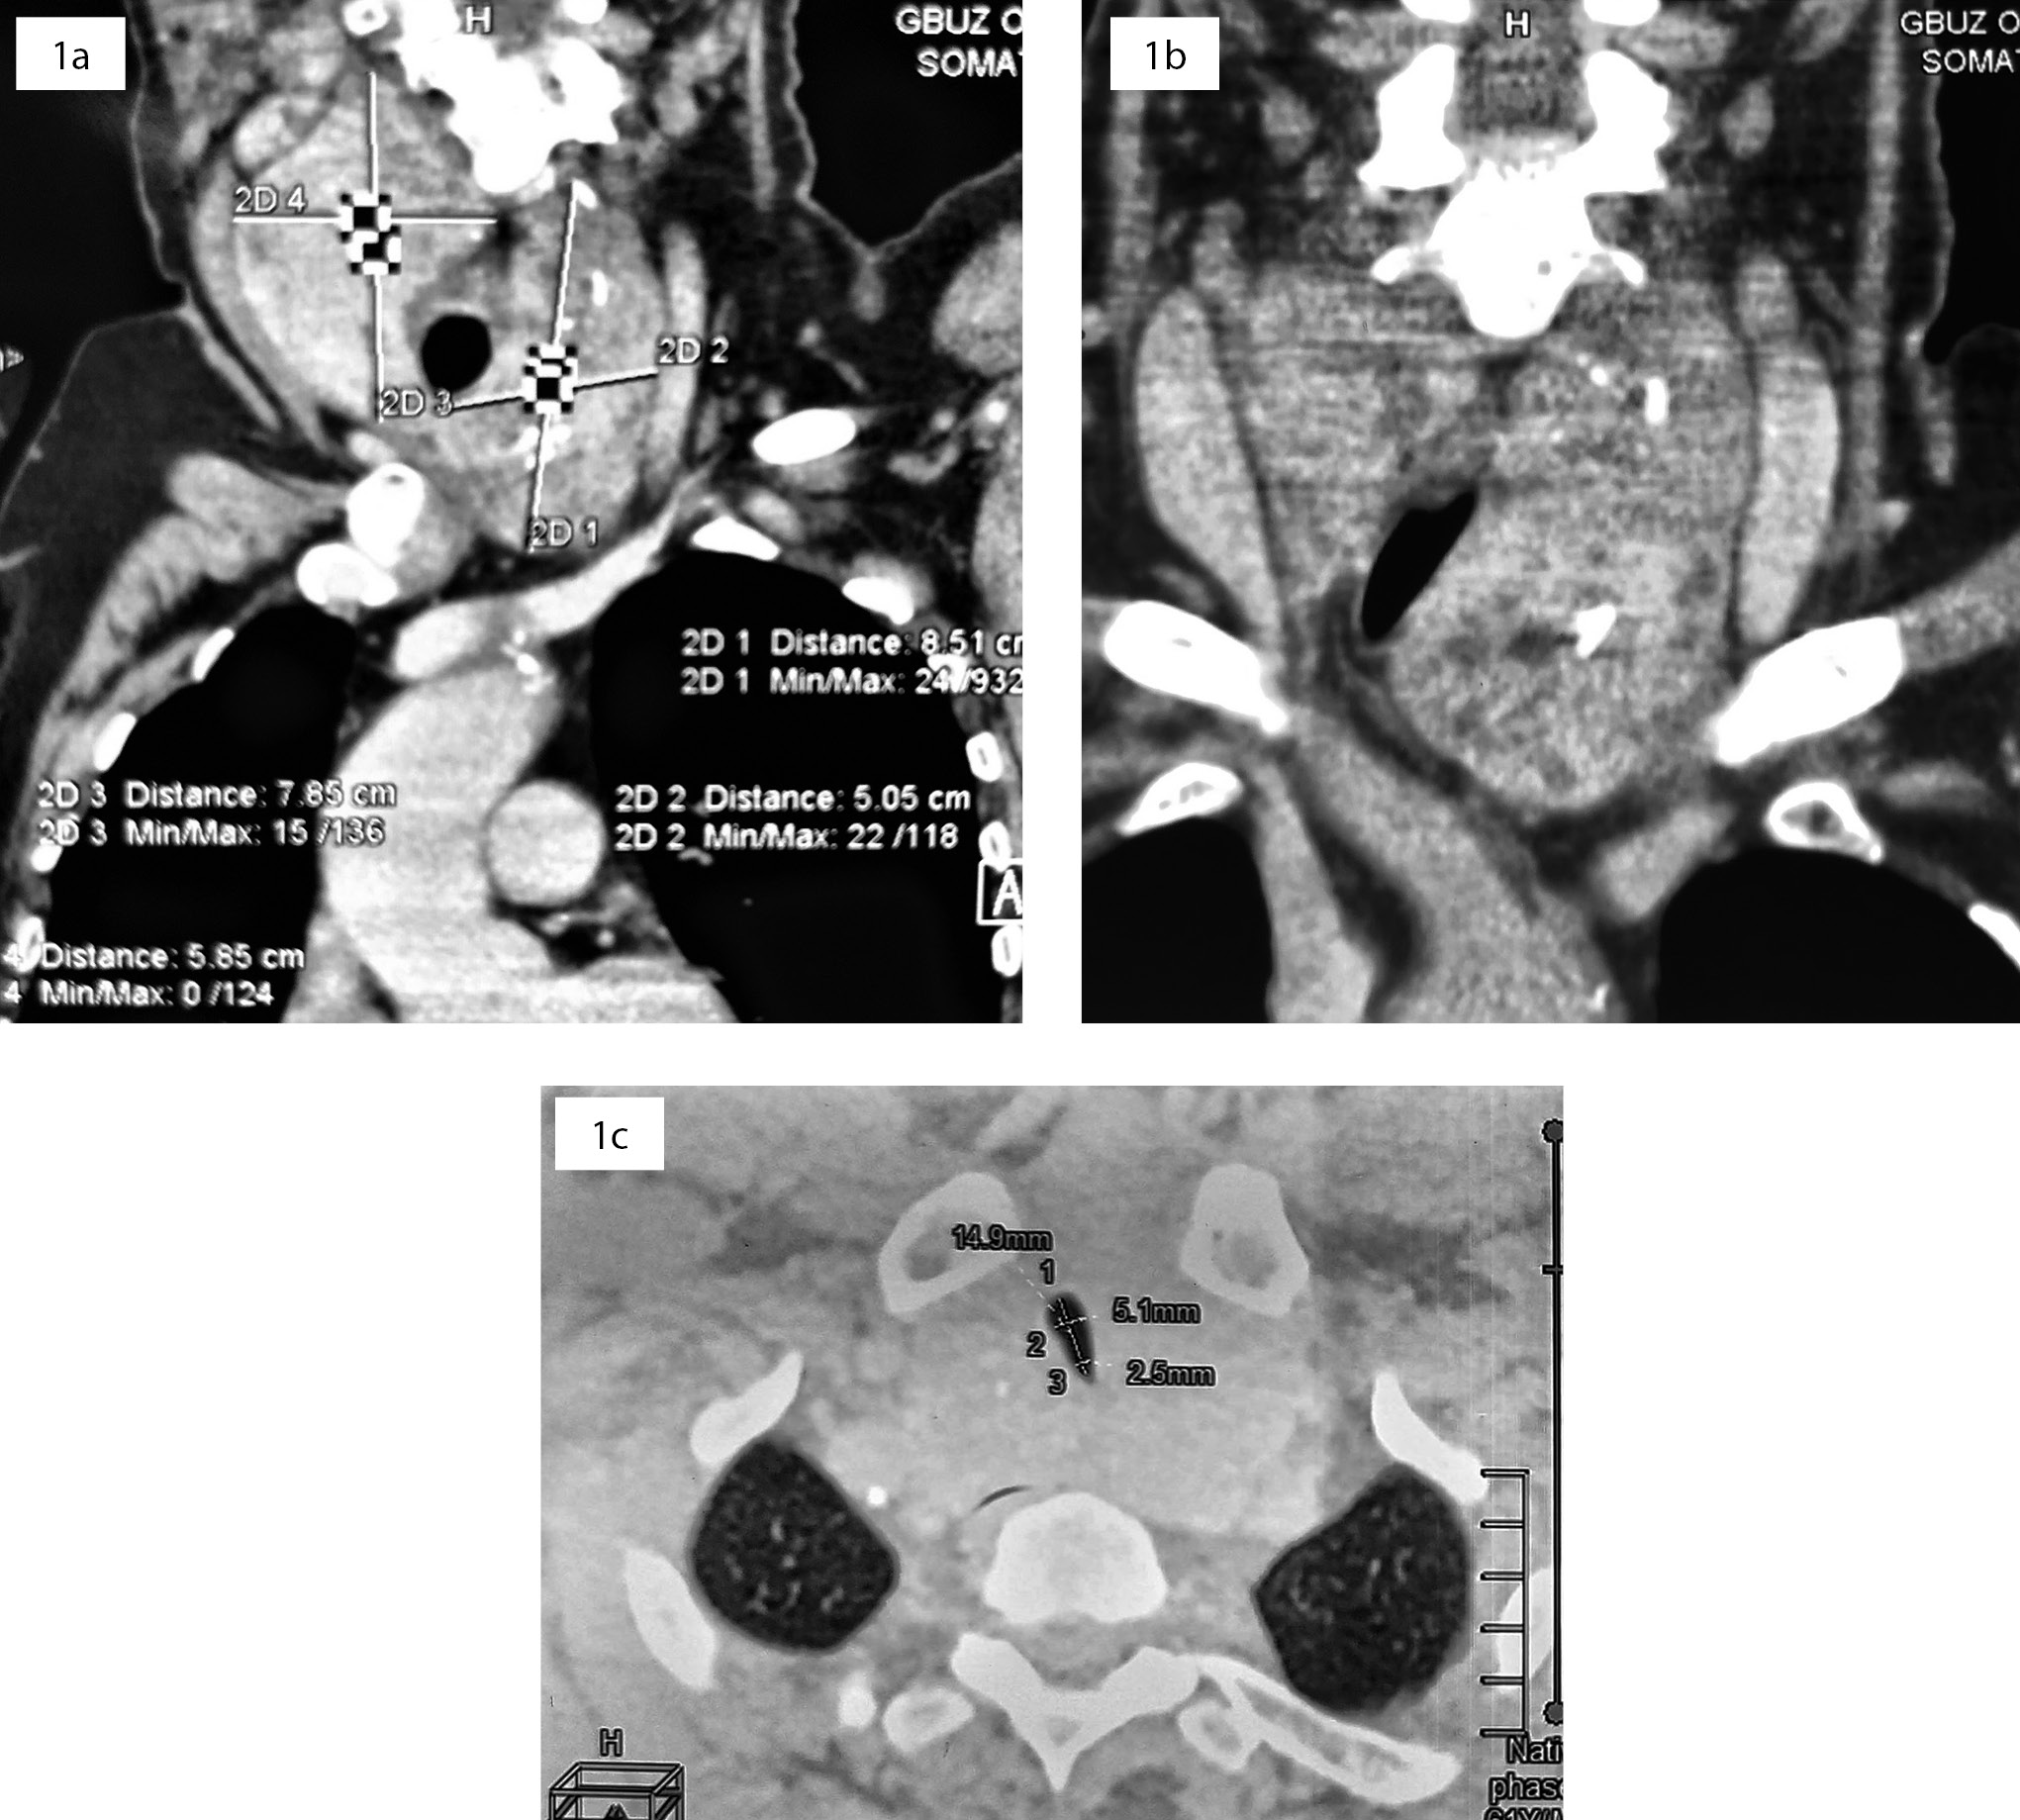

1. Рисунок 1. Компьютерная томография шеи. 1a — сагиттальная проекция; 1b — фронтальная проекция; 1с — аксиальная проекция: диффузное увеличение щитовидной железы за счет обеих долей с распространением загрудинно. Верхние полюса достигают сосцевидных отростков. Сужение просвета трахеи до 5 мм.

Представлено клиническое наблюдение хирургического лечения пациента с многоузловым шейно-загрудинным зобом 2 степени по ВОЗ, осложненным сдавлением трахеи (до 5 мм). Впервые диагноз многоузлового зоба был выставлен эндокринологом по месту жительства 3 года назад. В течение двух лет пациента беспокоили жалобы на затрудненное дыхание и одышку при физической нагрузке. Неоднократно в течение последнего года обращался к специалистам терапевтического профиля (терапевту, пульмонологу, кардиологу), однако ни один из них не смог объяснить причину затрудненного дыхания. После обследования у эндокринного хирурга было выявлено осложненное течение много- узлового зоба с развитием компрессионного синдрома шеи с сужением трахеи. По данным ультразвукового исследования, щитовидная железа диффузно увеличена в размерах, преимущественно за счет левой доли с общим объемом 132,5 см3; по данным компьютерной томографии — трахея смещена вправо за счет компрессии левой долей, просвет сужен до 5 мм. Выставлены показания к оперативному вмешательству по жизненным показаниям. Пациенту выполнена тиреоидэктомия. В послеоперационном периоде жалоб на затрудненное дыхание пациент не предъявлял и отмечал улучшение физической активности. Данное наблюдение показывает, что при ведении пациентов с многоузловым зобом врачу любой специальности необходимо помнить о проявлениях компрессионного синдрома шеи. Следует направлять таких больных как можно раньше на консультацию эндокринного хирурга, чтобы не упустить оптимальные сроки планового оперативного вмешательства.